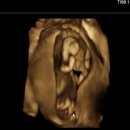

오늘은 소중한 아기를 맞이하기 위해 10주차에 서둘러 알아본 디에르 산후조리원 방문 후기를... 그럼 오늘 포스팅도 우리 예비맘들께 도움이 되었길 바랍니당 #성남산후조리원 #분당산후조리원...

And we go(20260224)